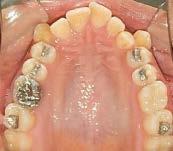

En las fotografías intraorales (Figura 3) observamos una clase II molar bilateral, clase II canina derecha, clase III canina izquierda, apiñamiento severo superior y moderado inferior, presencia de mordida abierta anterior y posterior a nivel de premolares (Figura 4), forma de arco triangular en la arcada superior y forma de arco oval en inferior, ausencia del OD 46 y presencia de un diente supernumerario.

En las fotografías oclusales observamos la forma de arco oval, la solución del apiñamiento y el cierre de la mordida abierta. (Figura 8)